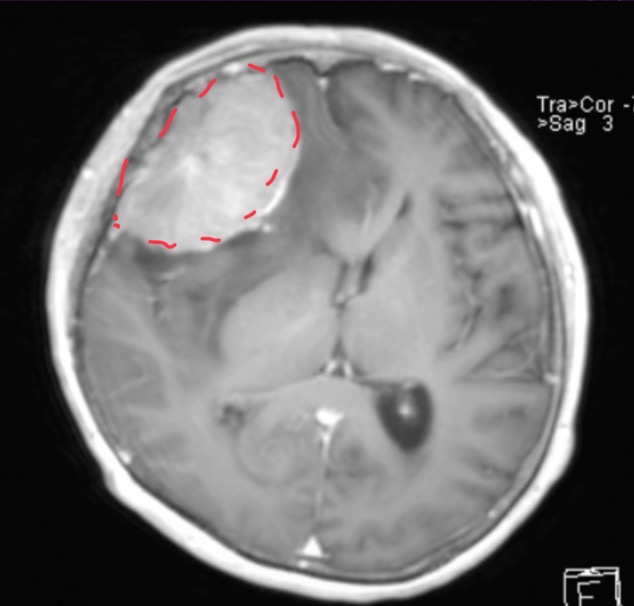

10-year-old male has a history of intermittent headaches for the past five months.

Pineoblastoma

Pineal gland tumor with mets to the frontal lobe